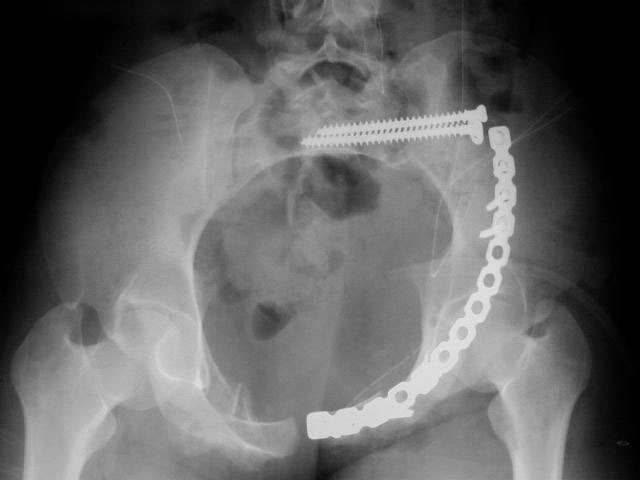

I did as suggested, I performed a 2-stage procedure (posterior sacral osteotomy and anterior take-down of left-sided rami fractures and anterior plate and percutaneous iliosacral screw fixation). It was a difficult and humbling experience. I felt as though the sacral osteotomy was complete and seemed so using intraoperative image views (inlet, outlet and true lateral of the sacrum) however after placing the distractor anteriorly I found that I could not see the sacrum well due to the bulk of the distractor itself. I then replaced it with radiolucent external fixation bars and noted widening of the left anterior SI joint.

Apparently my sacral osteotomy was not complete and the rotational correction (lateral and inferior) was occurring through the SI joint, at least anteriorly. An intraoperative x-ray showed definite improvement of the leg length discrepancy but not complete. I felt that in addition to the rotational correction the left hemipelvis also needed to move inferior as well. Due to the patient's small size, traction on her left leg simply produced pelvic obliquity and I really did not have a way of placing well leg traction which would require a post and at the same time obtain adequate intraoperative image views. Long and the short is I accepted a less than perfect reduction but with leg lengths now with less than 1 cm difference clinically and radiographically and I fused her left SI joint. No post-op nerve deficits. It was definitely a learning experience.

Any and all feed back is appreciated. Postop pics enclosed.

Intraoperative fluoro can be misleading regarding deformity corrections...maybe consider plain films when needed. Notice this lady's external rotation of the left hemipelvis postop and its impact on the acetabular coverage...see the inlet(caudal) view with attention to the ischial spine assymetry.